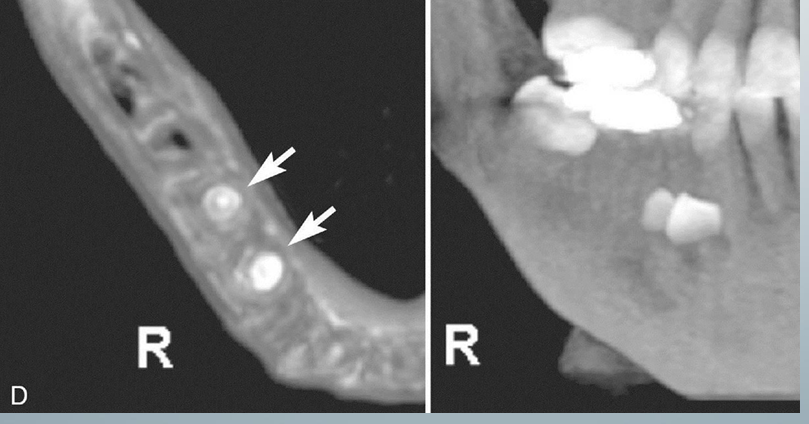

extraction treatment planning

-A is a cross-sectional view

-B is third-party software used to demonstrate the location of the inferior alveolar canal to an impacted third molar in 3D images

-C is an MPR reformatted image using proprietary software demonstrating the proximity of the root of an unerupted and impacted third molar associated with the IA canal